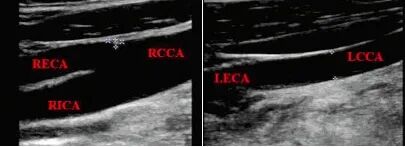

此時(shí)進(jìn)行頸部血管超聲檢查,發(fā)現(xiàn):雙側(cè)CCA管徑不對(duì)稱,RCCA管徑9.5 mm,向上分出RECA后,延續(xù)為RICA;LCCA管徑4.5 mm,向上未見分叉,直接延續(xù)為LECA,LICA管腔未顯影,如下圖,頸部血管超聲提示LICA先天未發(fā)育。